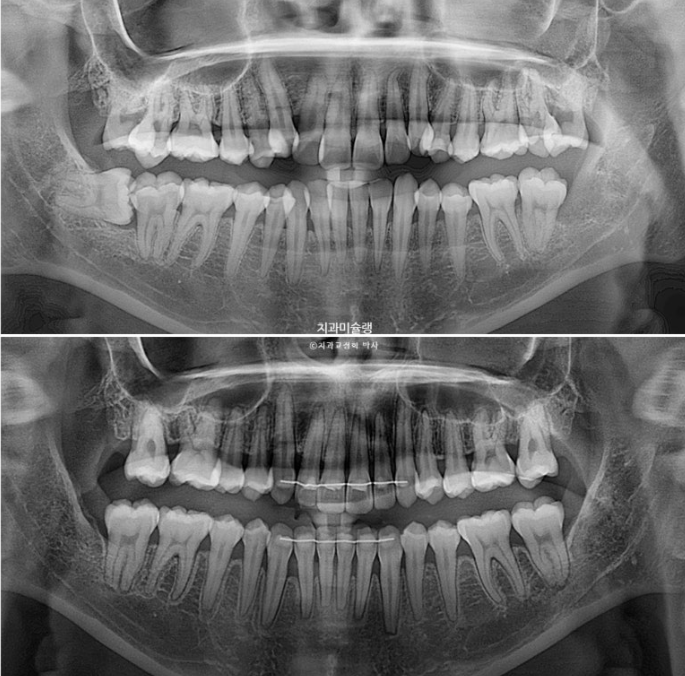

치근흡수는 없고 치근평행도는 좋습니다.

특히 사랑니 및 제 2대구치 발치공간으로 계획만큼 후방이동한 치아들이 눈에 띕니다.

23.08~25.10